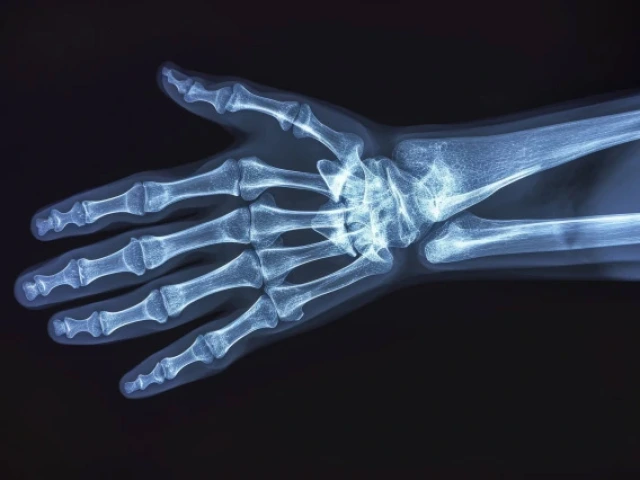

Orthopaedic Surgery Fellowship Programs Sports Medicine Fellowship Sports Medicine Fellowship Hand Fellowship Hand Fellowship Adult Reconstructive Fellowship Adult Reconstructive Fellowship For fellowship information, please contact:Maralyn Enriquezmenriquez@ortho.arizona.edu